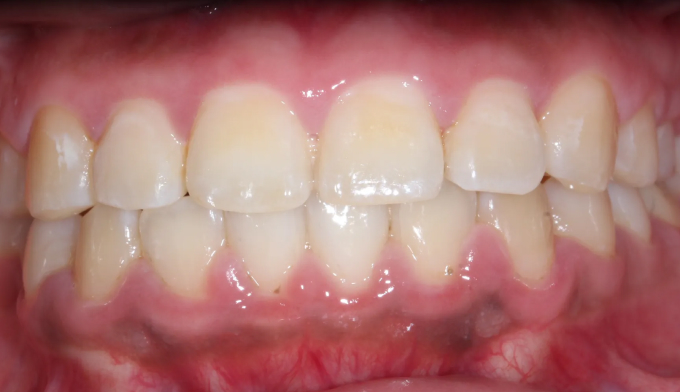

돌출입과 불규칙한 앞니를 가지고 있습니다. 그리고 아래쪽에 ‘임플란트’가 있습니다.

후방이동이 불가하므로 악궁확장을 통하여 공간확보를 시도하였고, 동시에 돌출감도 해소되었습니다.

최종적으로 임플란트의 존재때문에 중심선을 맞추지는 못했으나 환자분은 너무 만족해하셨습니다.